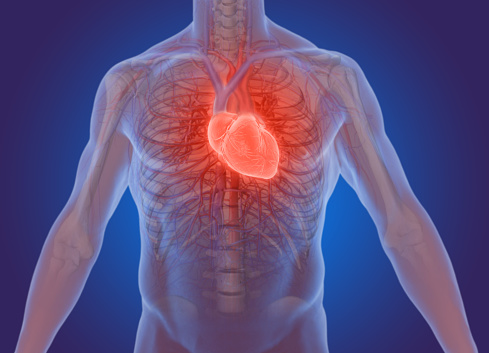

Breakthrough treatment for a common heart problem

Cardiac arrhythmia—which is an irregular heartbeat where the heart beats too fast or too slow—is a common condition. Although most arrhythmias are harmless, some can be quite serious and even life threatening, as the heart may be unable to pump a sufficient supply of blood to the organs and tissues in the body resulting in ...click here to read more